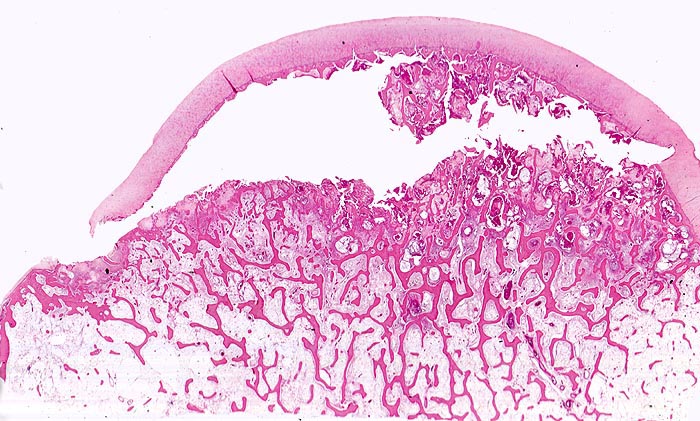

Makroskopisch ist die Nekrose im Anfangsstadium durch eine intensiv gelbe Verfärbung mit hämorrhagischem Randsaum charakterisiert. Häufig kommt es zur flächenhaften Ablösung des ansonsten intakten Gelenkknorpels (DD Arthrose!) zwischen subchondraler Knochenlamelle und angrenzender Spongiosa. In den Spätstadien sind die Nekrosezonen grau-gelb gefärbt und von körniger Konsistenz. Ein Teil der nekrotischen Spongiosabälkchen dient als Leitschiene für die Neubildung von Osteoid und mineralisierten Trabekeln, die an der Aussenseite angelagert werden. In der Nekrosezone kommt es zur Sequestrierung von Knochenbälkchen durch Frakturen. Die Markräume werden bindegewebig organisiert. In der Peripherie besteht initial ein hyperämischer Randsaum und im Verlauf kommt es zur Ausbildung einer metaplastischen Knorpel- und Knochenneubildung mit Randsklerose. Das Endstadium der Abräumreaktion untergegangener Knochenabschnitte stellt eine meist subchondral lokalisierte pseudozystische Umwandlung dar. Schliesslich kollabiert der Femurkopf und der Verlust der Gelenkkongruenz führt zu einer fortschreitenden sekundären Coxarthrose (> 3192)

• Flächenhafte Ablösung des gut erhaltenen Gelenkknorpels zwischen subchondraler Knochenlamelle und angrenzender nekrotischer Spongiosa.

• In der Nekrosezone osteoklastäre Resorption von avitalen sequestrierten Spongiosabälkchen.

• Ortsständiger Lamellenknochen wird als Leitschiene zur Fasernknochenneubildung benutzt.

• Pseudozystische Hohlräume in den nekrotischen Markräumen.

• Fibrosiertes Mark mit einzelnen thrombosierten Arterien.